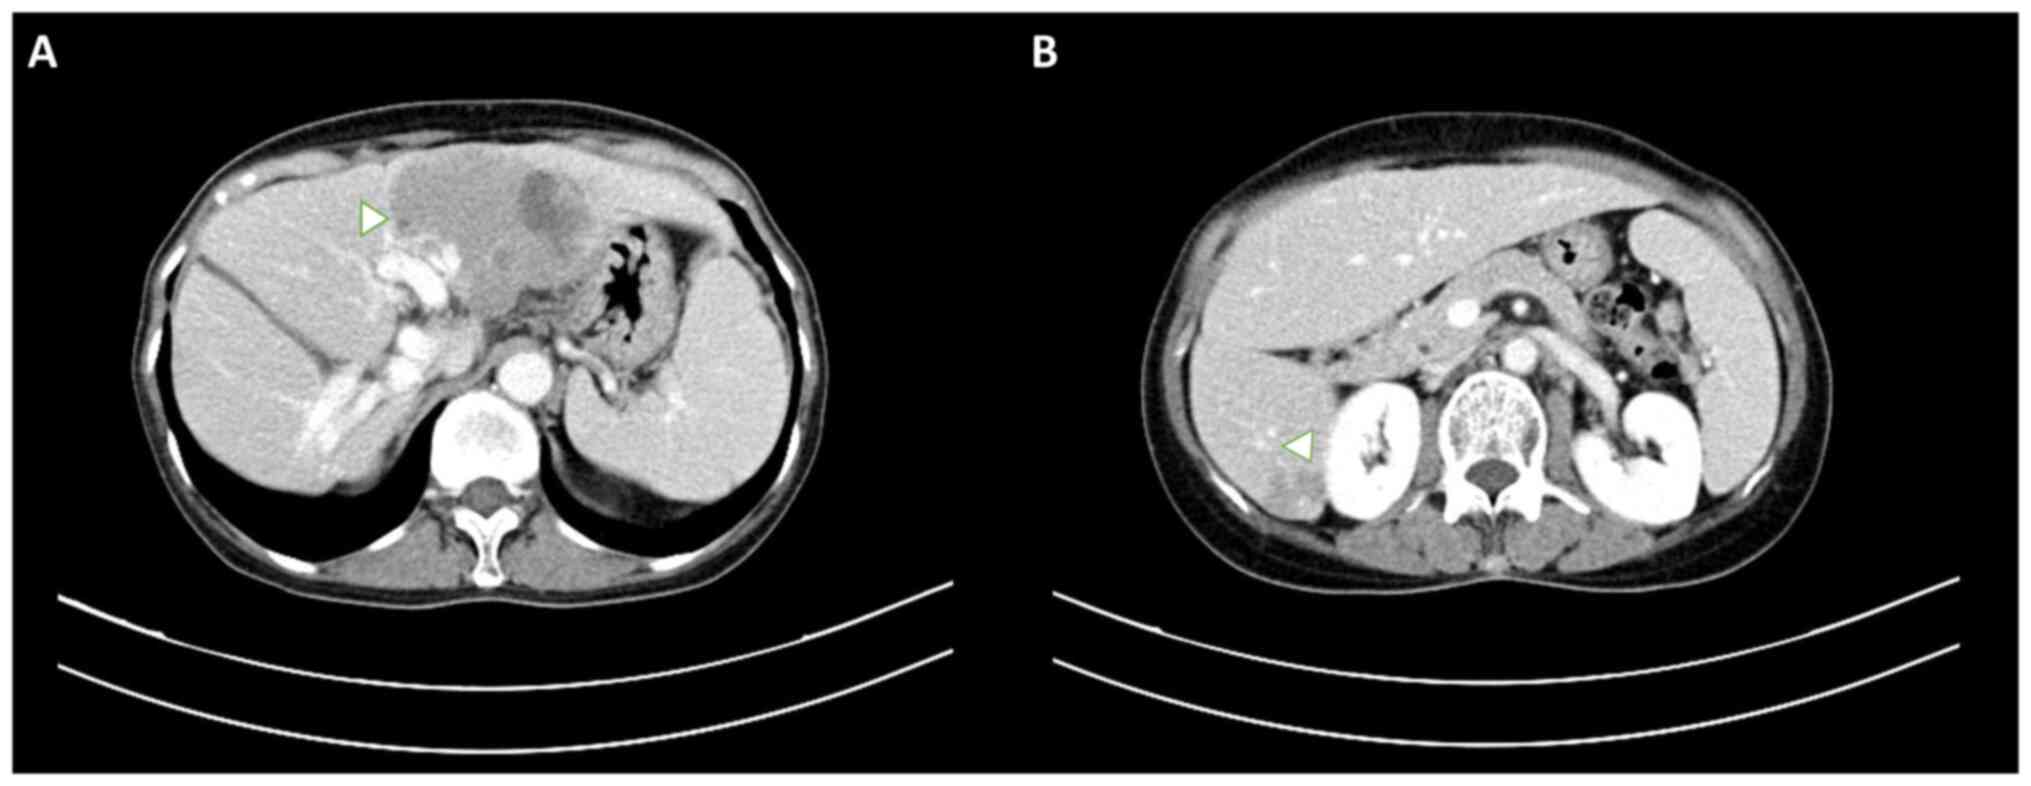

A 61-year-old woman with a history of Sjögren's syndrome, managed with hydroxychloroquine for 38 years, was diagnosed with CVID, and had been receiving intravenous immunoglobulin therapy since February 2023. In December 2023, the patient presented to the Emergency Department of Penghu Branch, Tri-Service General Hospital (Taiwan), with shortness of breath that had progressed over several days. Abdominal ultrasonography incidentally revealed two hypoechoic masses in the left lobe of the liver (Fig. 1). Subsequent dynamic abdominal computed tomography (CT) revealed two hypo-enhanced lesions located in liver segments 2/4a and 6 (Fig. 2), which were initially misdiagnosed as hepatocellular carcinoma due to their non-specific radiological features. The patient's tumor markers, including α-fetoprotein and carbohydrate antigen 19-9, were within normal limits. Additionally, liver function tests, including those for alanine aminotransferase (76 U/l; normal range, 7–56 U/l), aspartate aminotransferase (56 U/l; normal range, 10–40 U/l) and alkaline phosphatase (277 U/l; normal range, 44–147 U/l), showed mildly elevated levels, while the bilirubin levels (0.5 mg/dl; normal range, 0.1–1.2 mg/dl) remained normal. A sonography-guided liver biopsy was performed, and hepatic MZL was histologically confirmed based on strong CD20 positivity, a low Ki-67 proliferation index (~5%) and the absence of CD3 in neoplastic cells. Focal positivity for CD10 was also observed (Fig. 3). Samples were fixed in 10% neutral buffered formalin at room temperature for 24, sectioned to 4-µm and then stained with hematoxylin (room temperature for 5 min) and eosin (room temperature for 2 min), before being observed by light microscopy. For immunohistochemistry, the sections were incubated with anti-CD20 (dilution 1:100; cat. no. ab9475; Abcam), anti-CD3 (dilution 1:100; cat. no. ab16669; Abcam), anti-CD10 (dilution 1:100; cat. no. NCL-L-CD10-270; Leica Biosystems) and anti-Ki-67 (dilution 1:200; cat. no. ab16667; Abcam) primary antibodies at room temperature for 1 h and then with biotinylated secondary antibody (horseradish peroxidase-conjugated; dilution 1:200; cat. no. ab6720; Abcam) at room temperature for 30 min. Light microscopy was used for observation.

Figure 1.

Abdominal ultrasonography showing two hypoechoic masses in the left lobe of the liver, incidentally identified during routine imaging. (A) Transverse view showing the larger hypoechoic mass with well-defined margins. (B) Longitudinal view highlighting the second hypoechoic mass with a heterogeneous echotexture.